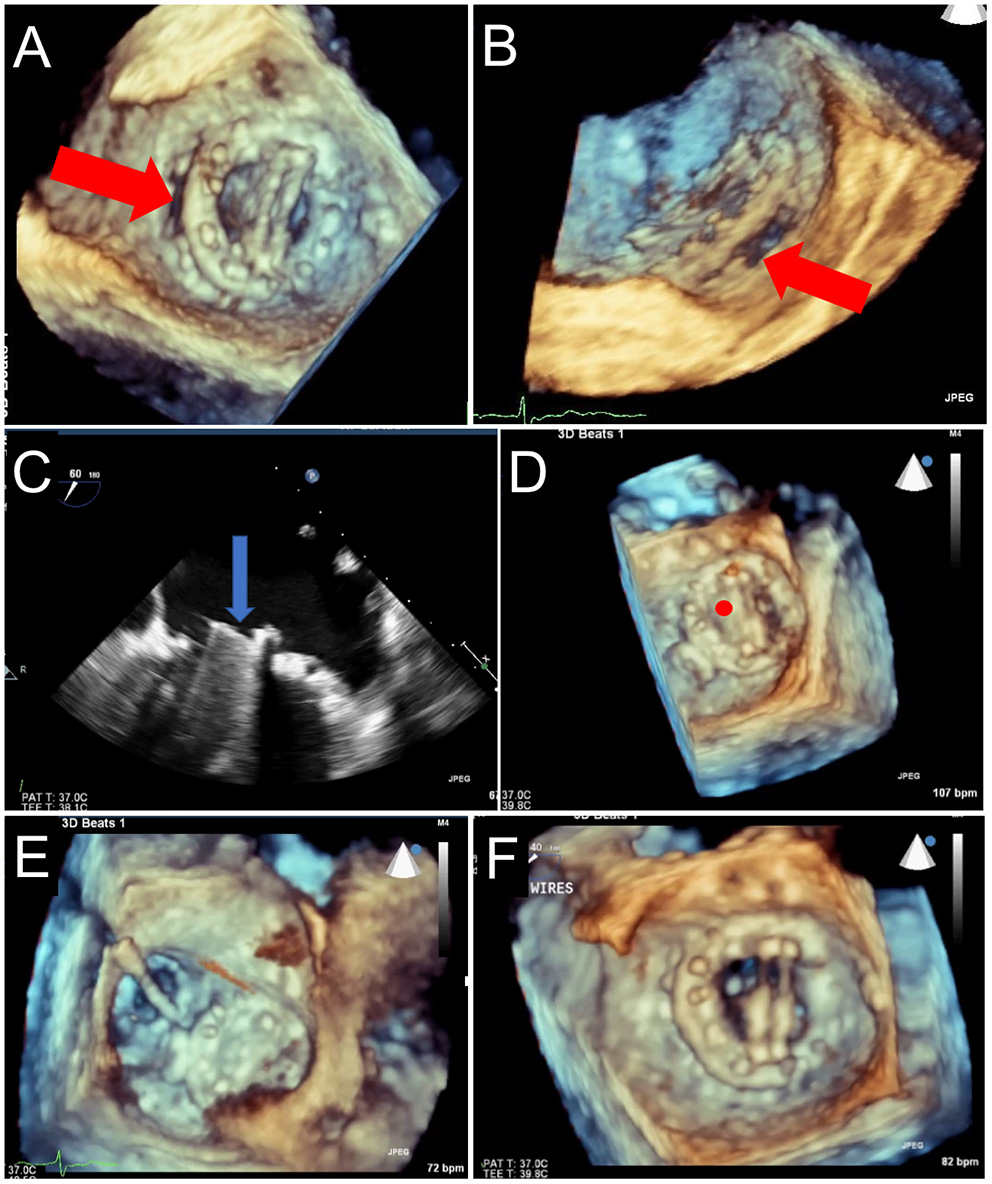

Figure 13

Prosthetic Mechanical Leaflet Dysfunction Following PVL Closure. A large lateral paravalvular defect is seen (red arrows) from the surgical (A) and lateral (B) view. While initial deployment was successful, once the closure device was released from the delivery system, the lateral mechanical leaflet no longer opened during diastole due to interference from the ventricular aspect of the closure device (C, blue arrow, and D, red circle). After snaring to remove the closure device (E), leaflet motion returned to normal (F).